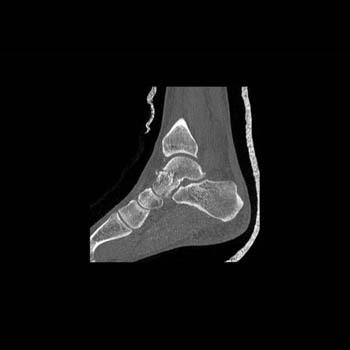

Clinical History: 12 year old female who fell down steps. She presents with left lower extremity pain.

CT Findings: Nondisplaced triplane left ankle fracture involving medial malleolus, with opened epiphysis.

Diagnosis: Minimally displaced of the medial malleolus and widening of the epiphyseal plate defined.